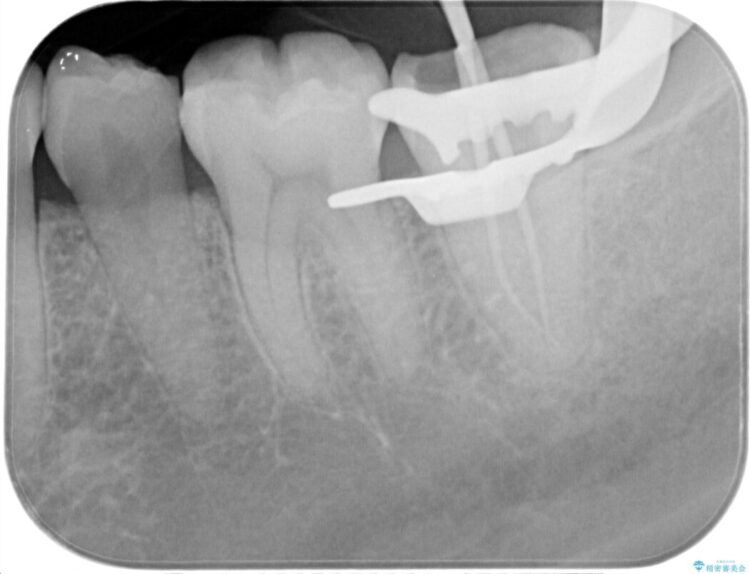

樋状根(といじょうこん)を根管治療

歯髄診にて患歯を特定し、不可逆性歯髄炎の診断のもと根管治療を行いました。

治療中、過去に修復された材料の下に虫歯を認めましたが、破折線はみとめられませんでした。